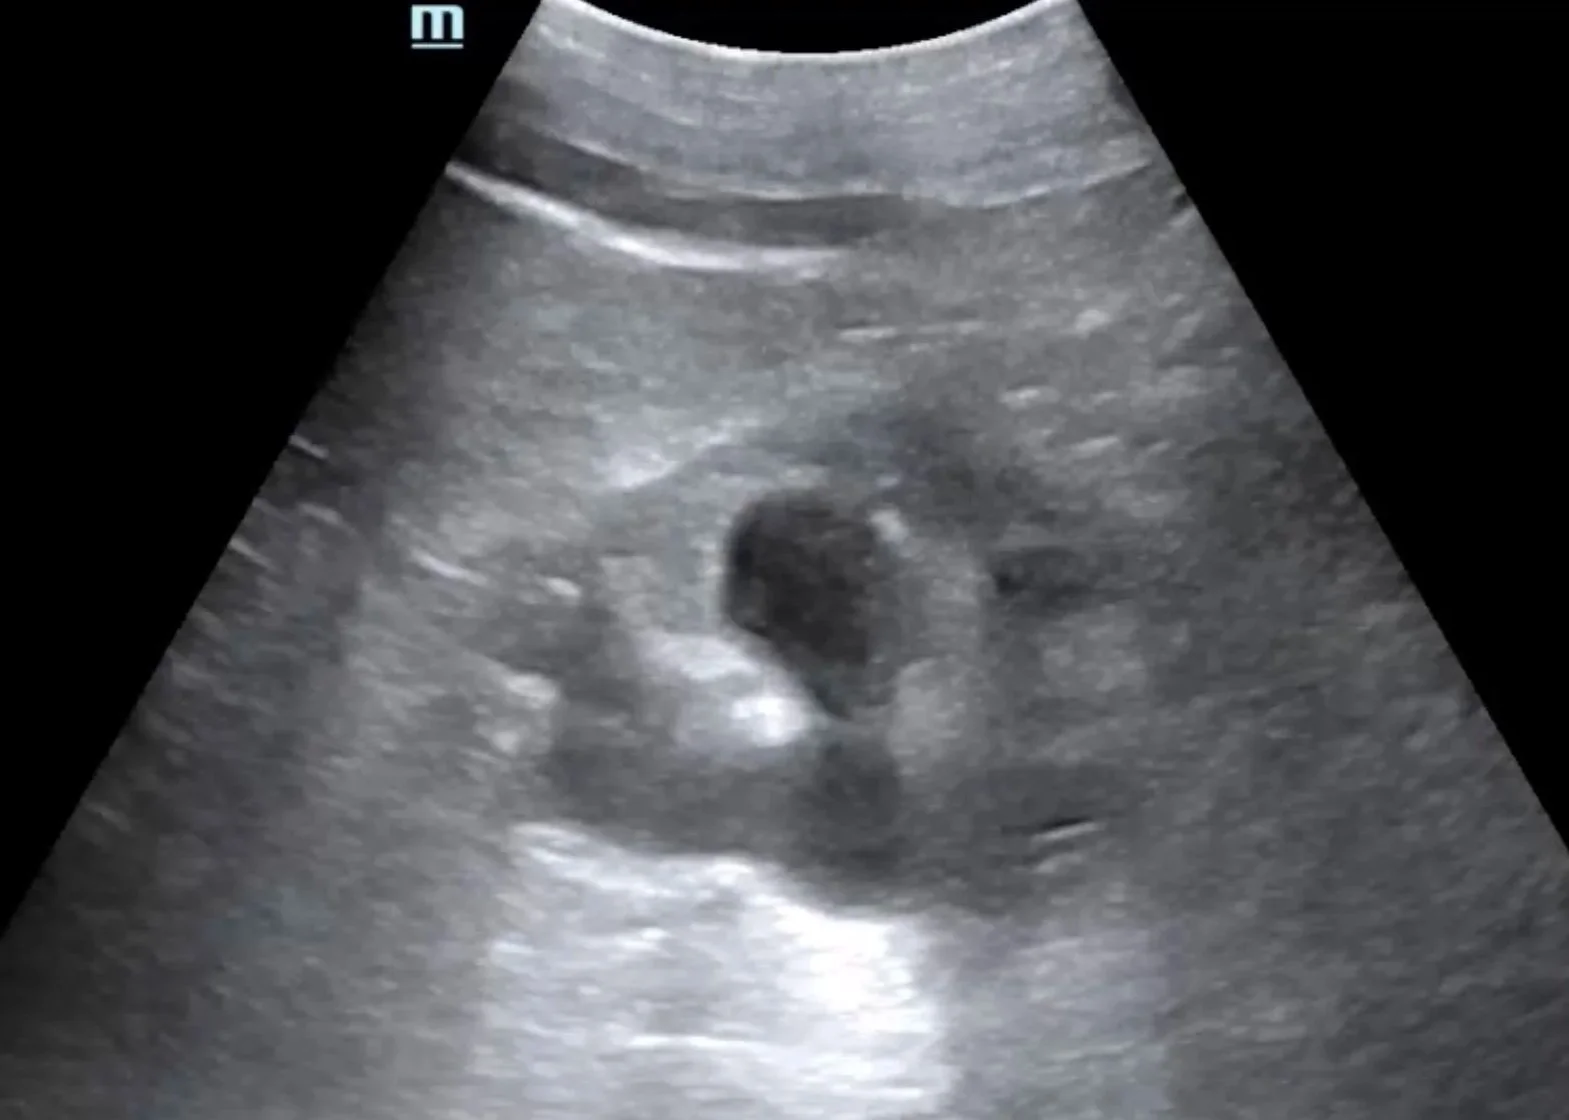

Intern Ultrasound of the Month: A Case of Hydronephrosis Leading to the Diagnosis of Tubo-Ovarian Abscess

Jun 6, 2023

Not all hydronephrosis is a kidney stone! Our latest Intern Ultrasound of the Month by Dr. Brooke Ott features a great case of a patient presenting with flank pain whose renal POCUS found hydronephrosis in addition to complex mass in her pelvis. This led to the discovery of tubo-ovarian abscess as the culprit. Learn more in this blog post!